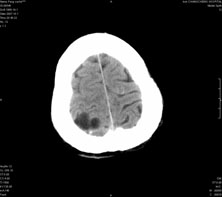

男,41岁,间断抽搐1小时,失神5分钟,bp130/90mmhg。低密度区ct值约16hu。

脑实质见多发散在的钙化点,左顶叶见一囊变灶,多考虑脑囊虫。

脑囊虫,部分囊内见头节。

脑实质见多发散在的钙化点,右颞、顶叶见囊性灶,考虑脑囊虫。

多发的囊泡(多发囊型)+多发的钙化(慢性钙化型)=混合型

顶叶最大的囊直径2.2cm,如果考虑囊虫的话,囊是不是有点儿太大了?